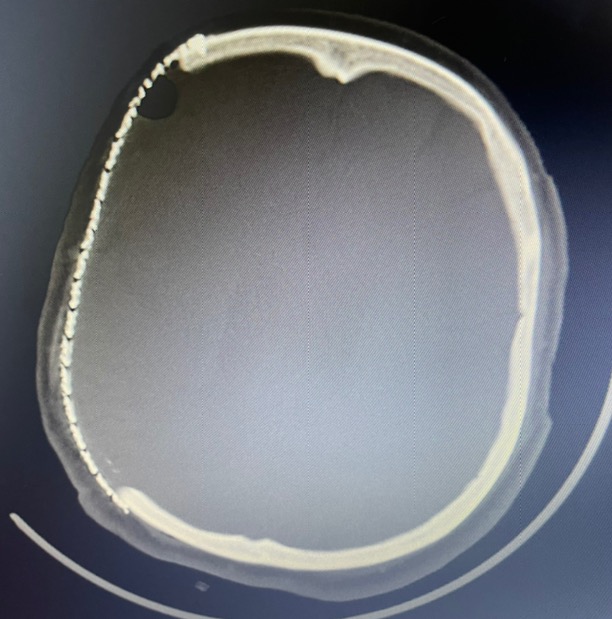

术后第一天复查

术后一月复查